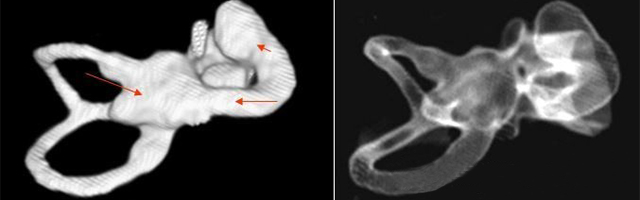

主要根據(jù)聽力學(xué)表現(xiàn)和影像學(xué)檢查。通過高分辨CT可看到耳蝸畸形。內(nèi)耳MRI顯示膜迷路內(nèi)水充盈,耳蝸扁平,耳蝸第二圈與頂圈間隔缺損,以及半規(guī)管、前庭的畸形。

先天性耳蝸畸形伴前庭和外半規(guī)管發(fā)育不良